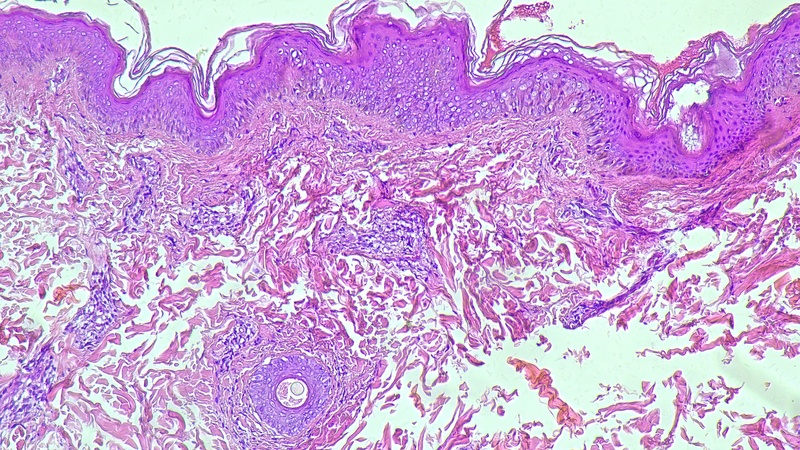

La lebbra è una malattia infettiva batterica cronica causata da Mycobacterium leprae, anche detta malattia di Hansen. Colpisce la pelle, gli occhi, il tratto respiratorio, ma soprattutto i nervi, che tendono a perdere la sensibilità nocicettiva, cioè la loro capacità di rilevare un possibile danno all’organismo. Si iniziano, quindi, ad avere lesioni o rash cutanei (non pruriginosi), ma anche macule, papule, noduli, o placche cutanee (spesso simmetriche). I pazienti sviluppano poi nel corso del tempo, con un’evoluzione che può durare decine di anni, lesioni anche gravi, a partire da bruciature, ferite o contusioni di cui non si accorgono, talvolta fino alla perdita delle estremità, ad esempio delle dita o del naso.